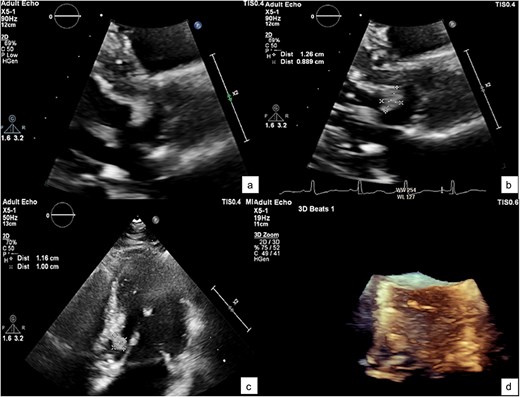

The patient underwent surgical excision of the LVOT mass via a median sternotomy. Cardiopulmonary bypass (CBP) was established using arterial cannulation in the ascending aorta and single, two-stage venous cannulation via the right atrium. An oblique aortotomy was performed to access the LVOT, and the mass was completely excised. The aorta was closed with 4–0 Prolene, and the excision site was inspected to ensure no residual tissue. Hemostasis was achieved, and CBP was weaned off once adequate cardiac function was confirmed. Two tube drainages in pericardial and mediastinal spaces. The pericardium was closed, with a total CBP time of 45 min, an aortic cross-clamp time of 27 min, and a total operative time of 3 h and 12 min. Gross pathology showed a 1 × 1 × 0.3 cm irregular, soft, grey-white polypoid mass. Histology examination of the mass revealed multiple branching papillary fronds with a central avascular collagen, lined by a layer of hyperplastic epithelial cells, consistent with papillary fibroelastoma (Figs 3 and 4).

A histological view of the excised mass reveals elongated and branching papillary fronds with central avascular collagen, lined by hyperplastic epithelial cells.